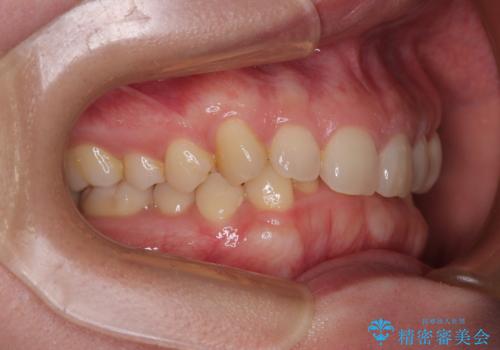

- 下顎前歯が完全に隠れてしまっていることを気にして来院された患者様です。

下顎の臼歯が手前に傾斜していることで咬み合わせが深くなってしまい、下顎前歯が見えないほどに上顎前歯が覆い被さっている状態でした。

下顎臼歯を起き上がらせるためにユーティリティーアーチを使用し、一気に深い咬み合わせを改善することができました。